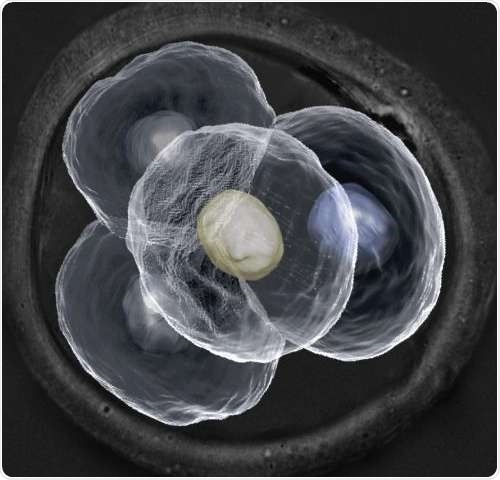

Microscopic image of a four-cell mouse embryo. Credit: Dr Nicolas Plachta

Contrary to the current conception that every cell within a preimplantation embryo is identical, the team of researchers at IMCB has demonstrated that the cells are in fact differentiated and may play very different roles in later development. By designing new cutting-edge real-time imaging techniques, the researchers were able to examine every cell within a preimplantation mouse embryo without perturbing its development. They observed differences in the way which certain proteins in each cell bind to their target genes. The scientists also observed that there were variances in cell behaviour at every stage of the embryo's development. As mouse embryos bear strong resemblance to human embryos at early stage development, the findings indicate that cells within a preimplantation human embryo are also not identical.